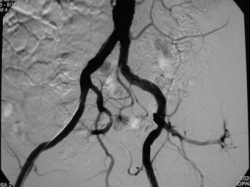

-  angiografie